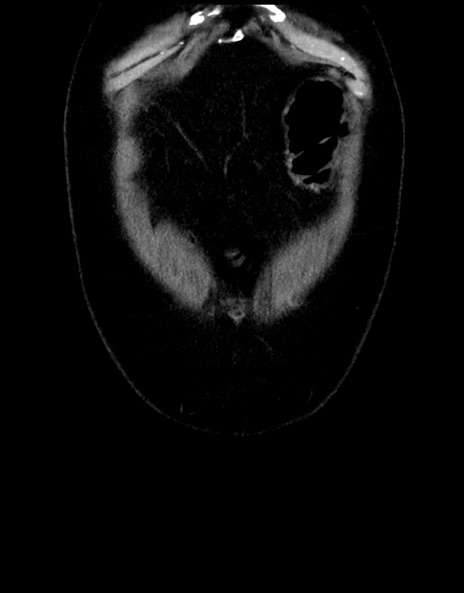

横断像